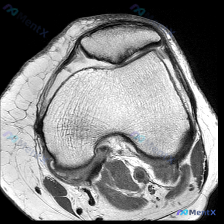

今天看到一个很有代表性的读片问题,整理一下思路分享给大家。 病例/问题背景 问题:针对一张标注怀疑「软骨异常」的膝盖MRI T1加权轴位图像,描述可见的视觉表现。 --- 影像基础信息 图像为单张膝关节水平面T1加权成像(T1WI),这个序列的基本信号特点是:骨髓、皮下脂肪呈高信号(亮),肌肉呈中等...